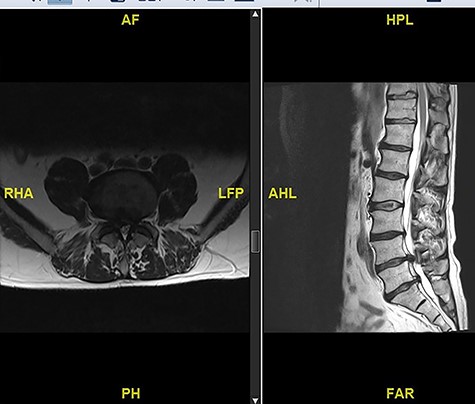

A 56-year-old male patient lumber decompression in a local neurosurgical centre for severe canal stenosis at L1/2 and L2/3 (Fig. 1) level after presenting with bilateral leg weakness and perianal numbness. Three months later he presented with recurrence of right leg pain radiating into the calf and worsening back pain as well as distal lower limbs weakness bilaterally with no sphincter problem. Following an magnetic resonance induction (MRI), which revealed a disc prolapse at L1/2 (Fig. 2), the patient was referred to our Centre. The images were reviewed by a consultant radiologist and as a possibly of intradural herniated disc disease was described. Intraoperatively no extradural disc prolapse was found, so midline durotomy was performed. Intradural disc herniation (IDH) was identified, which was communicating with the disc space through a midline defect in anterior dura (Fig. 3). This was removed extracted under the microscope. Post-operatively, he had a CSF leak needing re-suturing of dura. The patient did make a good post-operative recovery with no major sensory or motor deficits or sphincter disturbance.

Initial MRI images prior to index procedure revealing stenosis at L1/2 and L2/3.